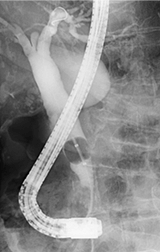

十二指腸鏡を用いて胆管・膵管を造影する検査をERCPといいます。内視鏡を口から挿入し十二指腸まで進めます。十二指腸にある胆管や膵管の出口(十二指腸乳頭)から胆管や膵管にカテーテルを挿入し造影剤を注入したり、処置具を挿入したりします。

総胆管結石の場合はバスケットカテーテルやバルーンカテーテルなどの処置具を用いて結石を除去します。通常の処置具では除去困難な巨大結石に対しては、胆管の中に細径の内視鏡(経口胆道鏡)を挿入し結石を衝撃波で破砕する治療を行います。

巨大な総胆管結石

経口胆道鏡を用いて

衝撃波で破砕

結石除去後